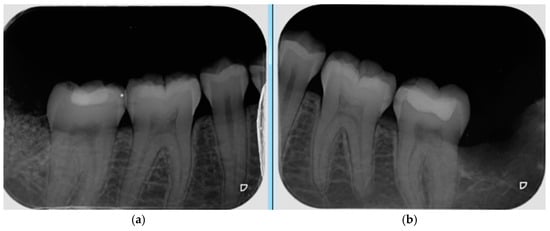

- Probing depth was measured 3 and 6 months after surgery at the DV, DM and DL points on the distal aspect of the second molar as shown in Figure 3.